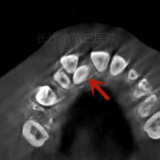

进一步检查后,唐俊发现,小明右侧门牙腭侧牙龈部分有一个小牙尖冒头,初步考虑这是一个多生牙;口腔CBCT(锥形束CT)三维成像检查证实了唐俊的判断:小明上前牙两个门牙之间有一个多生牙,多生牙的头在右侧门牙的腭侧,但是根却在两个门牙的两个牙根之间,而且根尖呈现近90°的弯曲。

原来小明的门牙间隙过宽,正是由于这颗位置独特的多生牙在作怪!